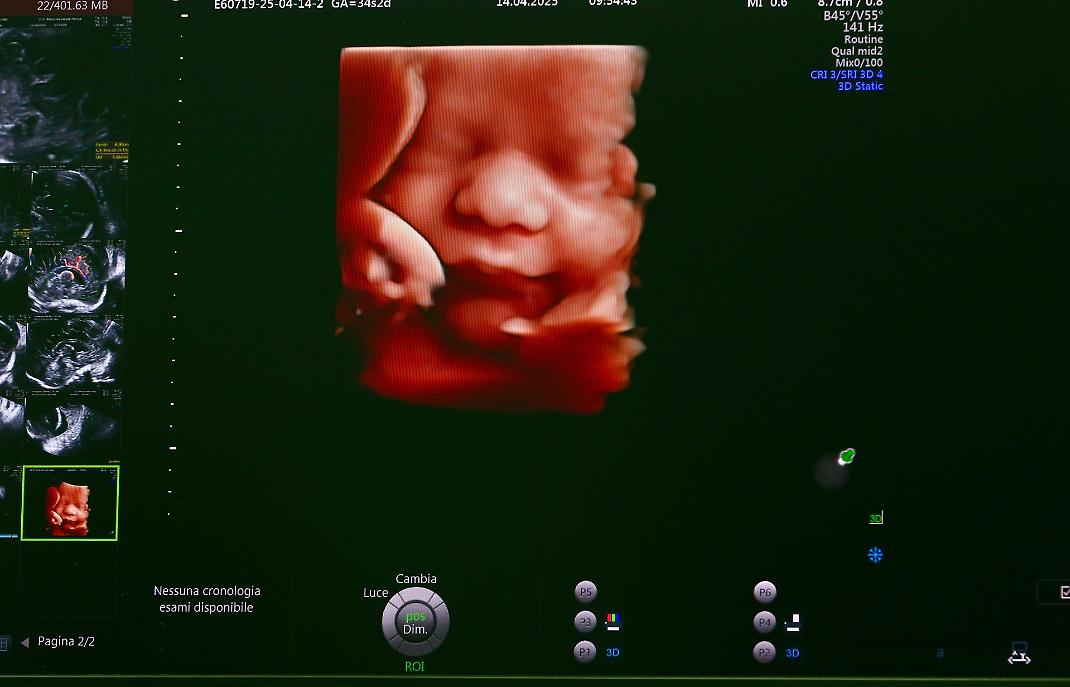

Anche il Servizio di Medicina fetale ha trovato nel “Sarcone” una nuova collocazione strategica. I locali dell’ex terapia intensiva, ristrutturati con 70.000 euro di investimento, ospitano ora spazi dedicati alle gravidanze a rischio, alle patologie fetali e alle gestazioni gemellari monocoriali. Nel biennio 2023-2024 sono state erogate oltre 17.000 prestazioni ambulatoriali, confermando il presidio come punto di riferimento per tutto il territorio.